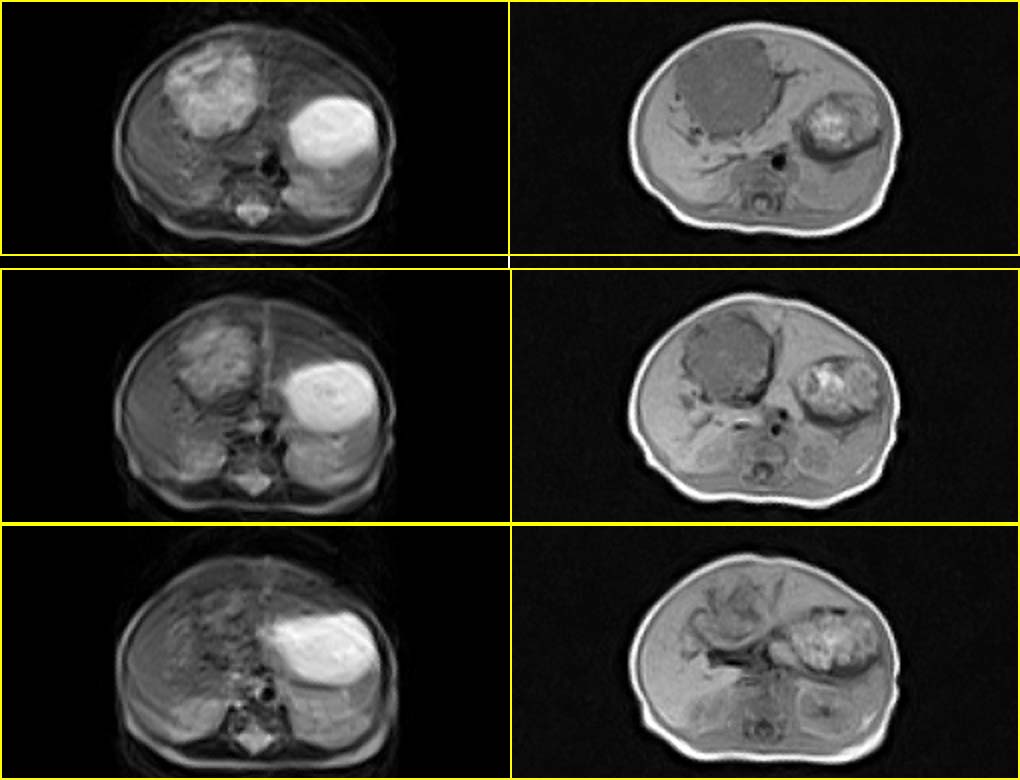

标题: PED0024:新生儿肝脏MR

患者男性,3天.

因生育前b超发现肝脏占位,怀疑血管瘤而行mr检查.

请分析您的诊断是否与b超诊断相同?